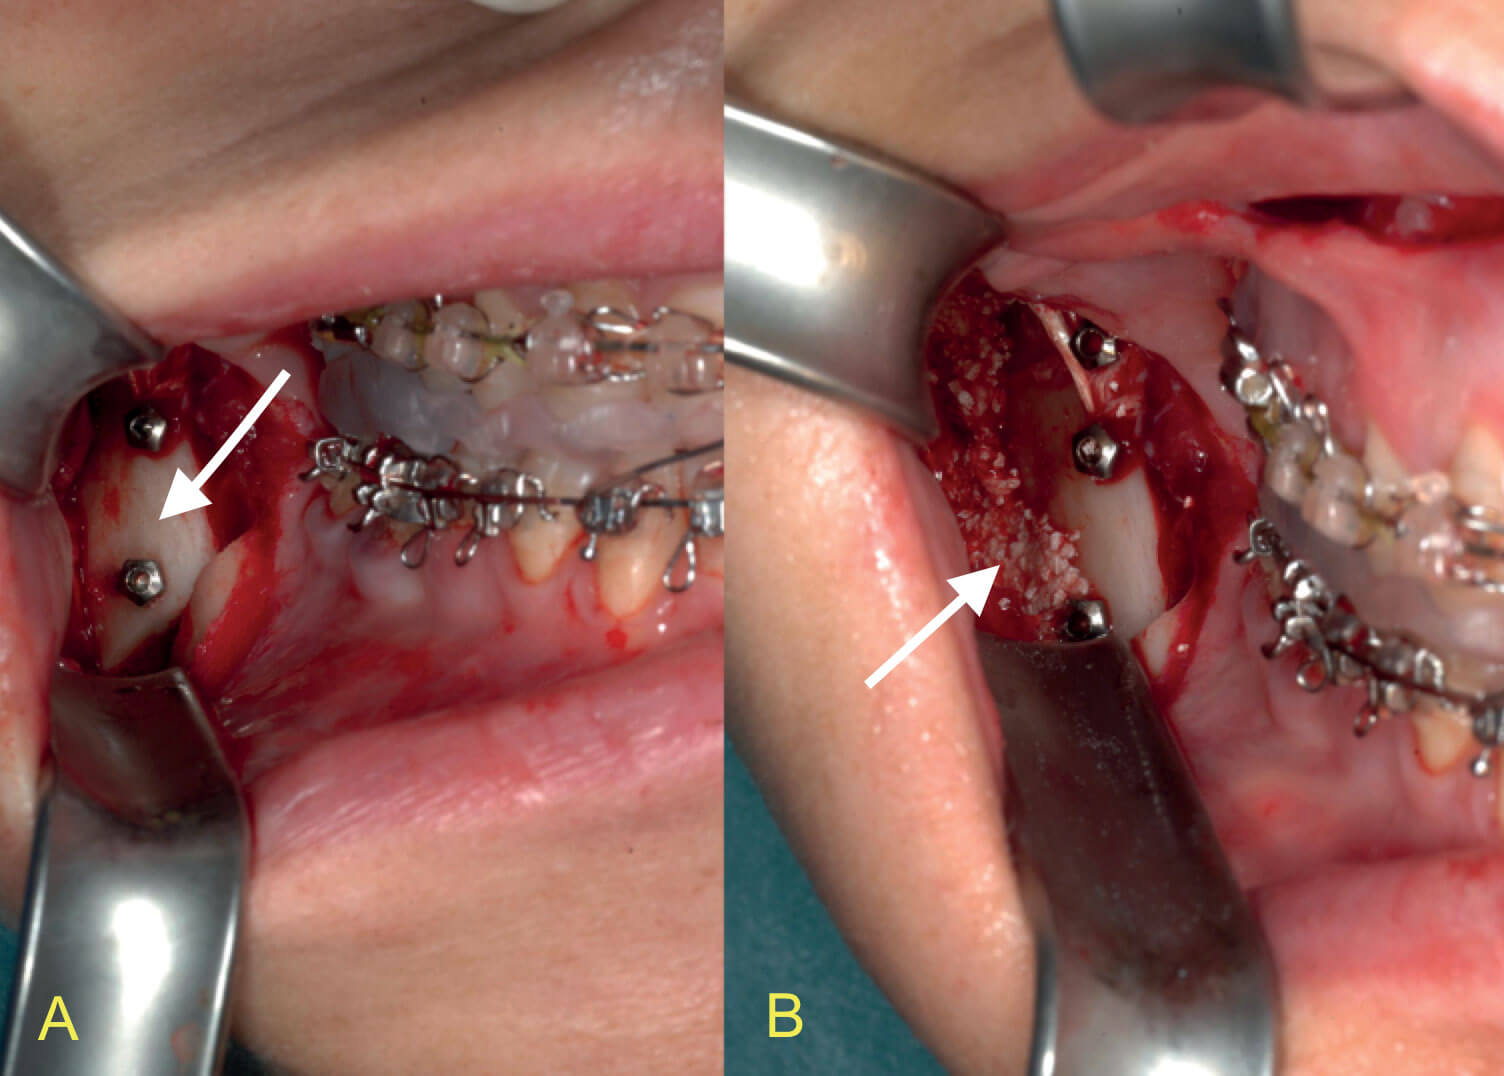

The gonial angle can be enhanced through a sagittal split osteotomy. This technique provides better results over HA-fibrin sculpting alone when posterior augmentation is required. After separation of the proximal (condylar) and distal (tooth bearing) segments, the latter part is positioned and secured to the maxillary teeth with the intermaxillary wafer. Then the condylar segment is positioned to achieve a favourable condylar head relationship in the glenoid fossa. At the next stage gentle clockwise rotation of the proximal segment is performed to optimise gonial projection. It is important to preserve the condylar position during this movement (Figure 4). Bilateral placement of a single screw to achieve rigid osteosynthesis allows the surgeon the option of quickly releasing the intermaxillary fixation and assessing the mandibular protrusive and lateral excursions to confirm correct condylar position prior to completing triple screw fixation. Contouring of residual interosseous gaps at the lower border or a desire to augment and increase the lateral projection is achieved with the ‘HA-fibrin glue putty’ technique described above (Figure 5).

Figure 5: Intraoperative pictures of a clockwise rotation of the proximal segment in a sagittal split osteotomy procedure. a) The vertical osteotomy site with screw fixation in place. The condyle-bearing segment (arrow) is clockwise rotated and there is a visible gap at the height of the external oblique crest. b) The matrix of HA and fibrin glue to fill up the gap at the lower mandibular border and to augment the jaw angle laterally (arrow).